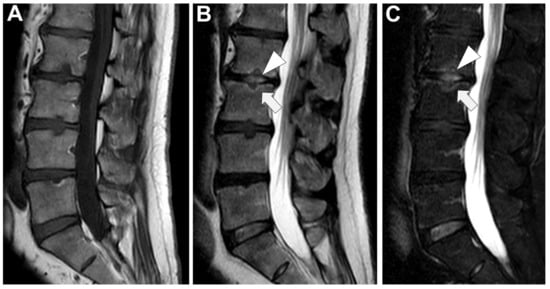

Figure 2. Conventional radiographs, lateral views (Panel A, and Magnification A1), of a 77-year-old male with previous pyogenic spondylodiscitis of T12-L1 vertebral bodies (partially collapsed and fused—arrows). Conventional radiographs, and lateral views (Panel B and Magnification B1) of a 64-year-old female with spondylodiscitis of L4–L5 vertebral bodies (thick endplate erosions are detected—arrowheads).

In the early stages of infection, specific radiographic markers are rarely evident, making it challenging to differentiate from degenerative pathologies. After 8 to 12 weeks, obvious destruction of bones can be observed (Figure 2) [32].

As the disease advances, observable changes include nonspecific osteopenic changes (demineralization) in the subchondral layer, erosive and blurred endplate margins, diminished intervertebral space, paravertebral soft tissue mass, resultant deformities, and noticeable soft tissue swelling.

End plate erosion is often subtle but recognized as the most reliable sign that can be detected on plain films and is the single most important observation to be made in evaluating any radiograph of the lumbar spine [30]. In cases of chronic infection, spinal deformities like kyphosis, scoliosis, or a combination of both may become apparent after approximately four months.